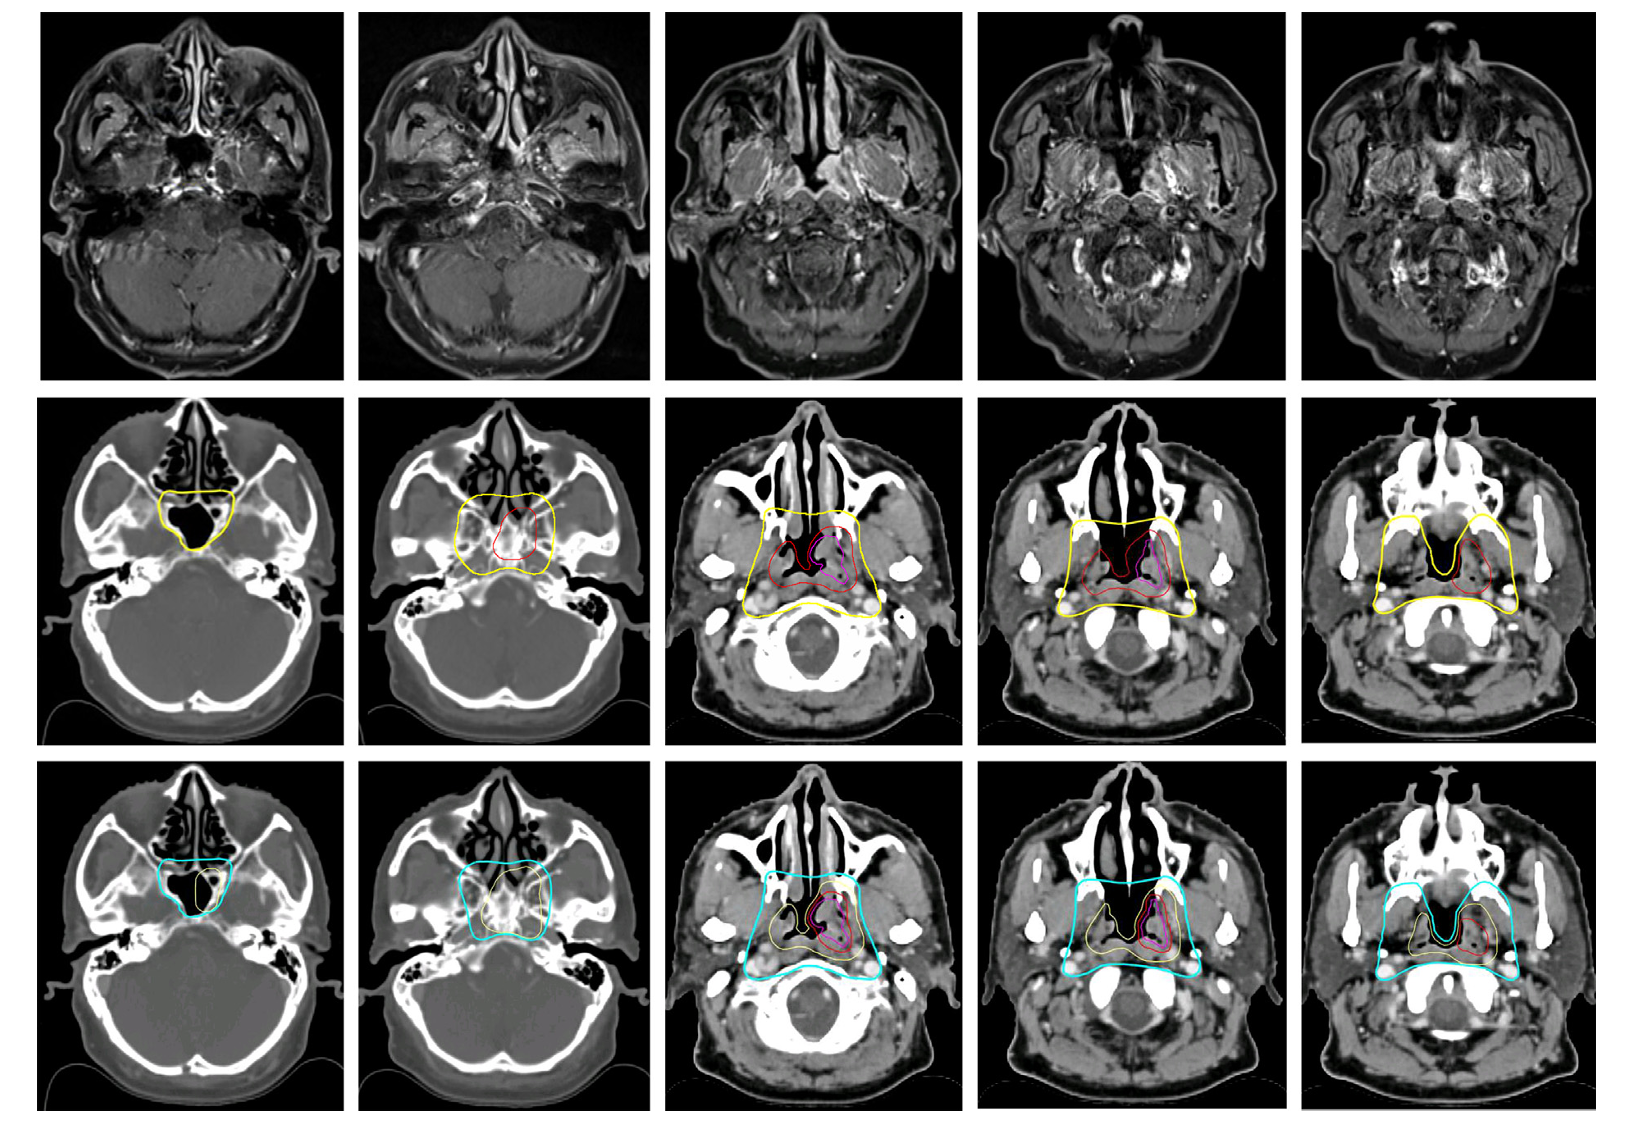

图1 T1偏侧肿瘤原发临床靶区的勾画

在低危靶区至50戈瑞等效剂量的勾画中,新版指南体现了基于肿瘤实际侵犯范围和邻近结构风险逐步考虑的核心理念,对于偏侧性肿瘤可以考虑豁免对侧结构的覆盖。具体而言,指南推荐对所有病例覆盖后鼻孔五毫米以内的后鼻腔和后颌窦五毫米区域,并将处方剂量设定为50戈瑞等效剂量,同时双侧翼突过程和咽旁间隙包括茎突后间隙仍建议常规覆盖,但剂量统一降至50戈瑞等效剂量。在筛窦方面,建议覆盖后部以确保包括犁骨,而对于蝶窦则推荐覆盖下五至十毫米部分,仅在明确受累时才覆盖整个蝶窦。海绵窦的覆盖策略保持不变,即T1至T2期肿瘤可以豁免,而T3至T4期肿瘤则需要覆盖受累侧,剂量同样为50戈瑞等效剂量。在颅底孔道的处理上,破裂孔仍建议双侧常规覆盖,而卵圆孔则可以根据肿瘤是否偏侧采取双侧或仅同侧覆盖,圆孔和岩尖的覆盖存在意见分歧,部分专家支持仅对偏侧肿瘤进行同侧覆盖。斜坡的覆盖策略为如果未受累则仅覆盖前三分之一,如果受累则覆盖全部,处方剂量为50戈瑞等效剂量。